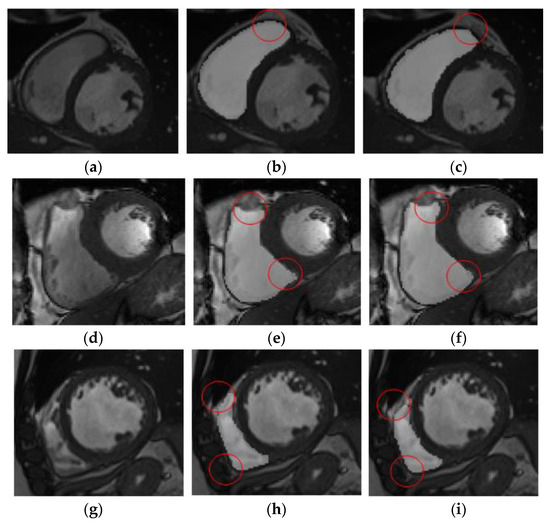

The results of right ventricle segmentation by the U-Net network are shown in Figure 5, which shows three groups of images, each of which is divided into three pieces. Figure 5a,d,g shows the input feature image, Figure 5b,e,h, which are the resulting images of the U-Net network segmentation, and Figure 5c,f,i is the gold-standard image marked by experts.

It may be observed from Figure 5b,c that the result of network segmentation was consistent with the result image marked by experts. However, it may be observed from Figure 5e,f that the network-segmented and expert-labeled images were under-segmented at the apex of the heart. It may be observed from Figure 5h,i that the network-segmented image and expert-labeled image exhibit the problem of over-segmentation near the ventricular wall. The position shown in the red circle represents the difference between the gold-standard image and the segmentation prediction area. Therefore, although the results of the U-Net network were feasible for segmentation of the right ventricle, there was an error in the segmentation of images with complex ventricular shapes.

Figure 5. Comparison of network segmentation results. (a) The input feature image. (b) The resulting images of the U-Net network segmentation. (c) The gold-standard image marked by experts. (d) The input feature image. (e) The resulting images of the U-Net network segmentation. (f) The gold-standard image marked by experts. (g) The input feature image. (h) The resulting images of the U-Net network segmentation. (i) The gold-standard image marked by experts.